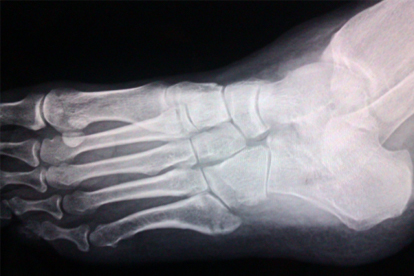

大腳骨手術(shù)后出現(xiàn)后悔情緒可能與術(shù)后恢復(fù)期不適、預(yù)期效果不滿意或并發(fā)癥有關(guān)。大腳骨手術(shù)通常指拇外翻矯正術(shù),術(shù)后可能出現(xiàn)疼痛、腫脹、活動(dòng)受限等情況,部分患者因康復(fù)過(guò)程漫長(zhǎng)或?qū)γ烙^改善效果失望而產(chǎn)生負(fù)面情緒。

建議術(shù)后嚴(yán)格遵循醫(yī)囑進(jìn)行康復(fù)訓(xùn)練,使用足踝支具保護(hù)關(guān)節(jié),避免過(guò)早負(fù)重??赏ㄟ^(guò)冷敷緩解腫脹,口服布洛芬緩釋膠囊、塞來(lái)昔布膠囊等藥物控制炎癥疼痛。若出現(xiàn)持續(xù)紅腫熱痛或關(guān)節(jié)畸形復(fù)發(fā),需復(fù)查X線評(píng)估骨骼愈合情況。心理上應(yīng)調(diào)整對(duì)手術(shù)效果的合理預(yù)期,必要時(shí)尋求心理咨詢幫助。術(shù)后6個(gè)月內(nèi)選擇寬松軟底鞋,避免高跟鞋或窄頭鞋,定期進(jìn)行足底筋膜放松按摩有助于功能恢復(fù)。